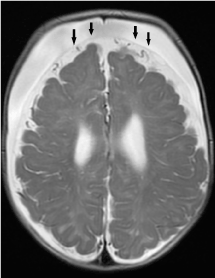

On T1-weighted images, non myelinated white matter is hypointense relative to cortical grey matter, providing a good contrast between cortical grey matter and subcortical white matter. However, between 4 to 8 months of age, gray matter and incompletely myelinated subcortical white matter are almost equal in signal intensity, resulting in blurring of the grey-white matter junction as well as pseudo-thickening of the cerebral cortex. One should not mistake this for MCD. During this period, the cortical ribbon is better depicted on T2-weighted images (Figure 15 a,b).

Figure 15. Pseudo-thickening of the cerebral cortex. (a) Axial T1-weighted image shows blurring of the grey-white matter junction in a 6-month old child. Between 4 to 8 months of age, gray matter and incompletely myelinated subcortical white matter are almost equal in signal intensity, resulting in blurring of the grey-white matter junction as well as pseudo-thickening of the cerebral cortex. (b) Axial T2-weighted image better delineates the grey-white matter junction in this age group.